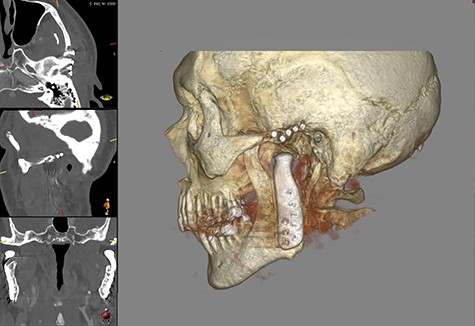

Shows postoperative CBCT after left TMJ replacement, 9 months after the right side.